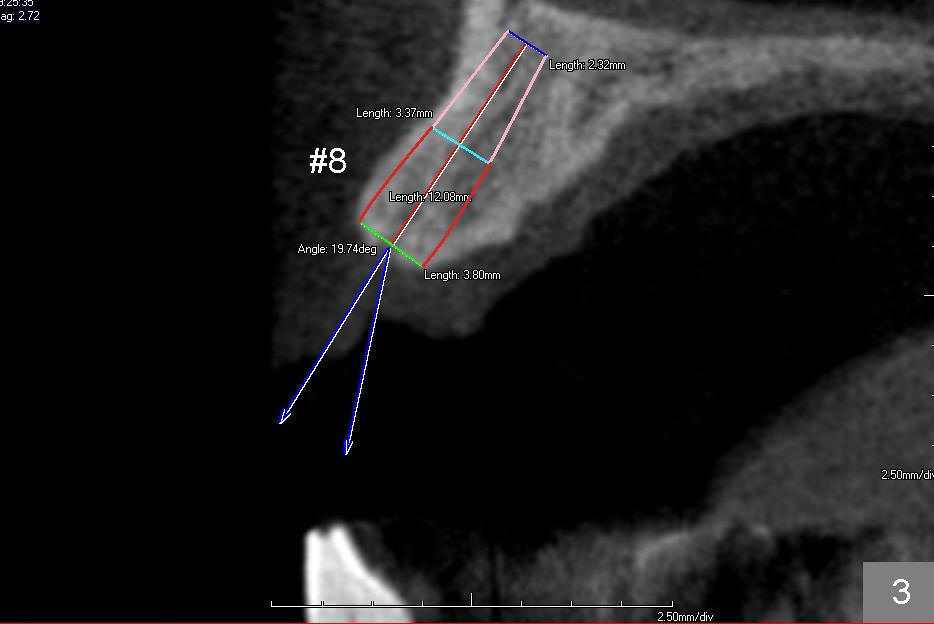

The second design is to place relatively smaller implants with the occlusion in mind (Fig.3,4). The starting point for the osteotomy will be as lingual as possible (especially Fig.4). The axis of the implant will be more parallel to the buccal plate. The angles of the angled abutments will be less (Fig.1 vs. 3; Fig.2 vs. 4). The cosmetic result may be better.

For the best trajectory, osteotomy at #8 should be initiated as palatally as possible (Fig.8 *). When a 4x11 mm 2-piece implant is placed, there is possibility that the apical buccal plate may be perforated (>). In contrast, a 3x11 mm 1-piece implant is more skinny with less coronal palatal thread exposure (Fig.9). The latter will be covered with bone graft and collagen dressing.